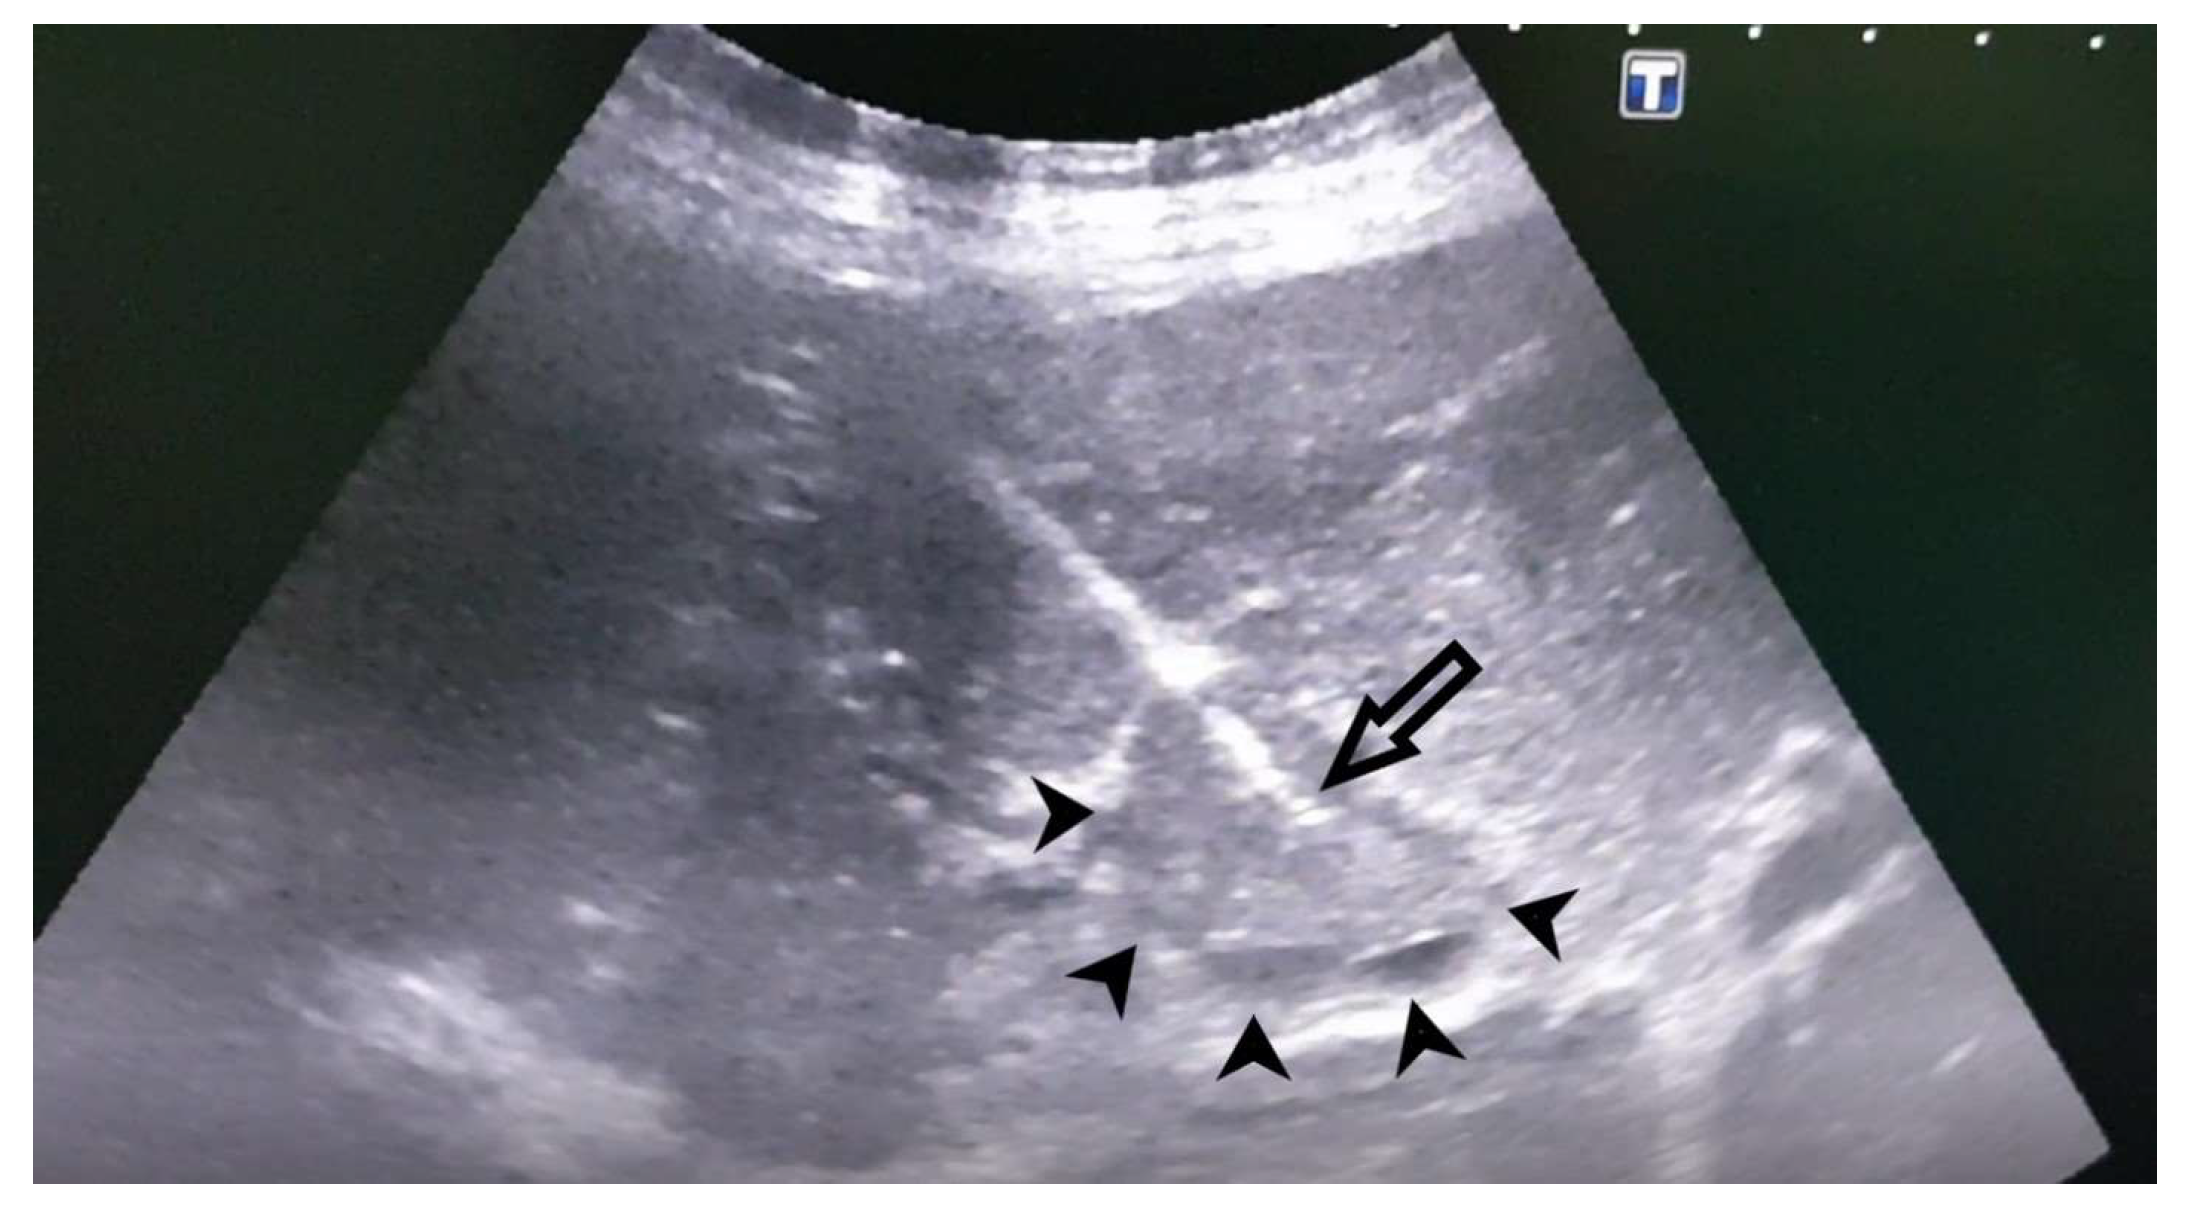

Figure 3. Ultrasound. PVT biopsy of the right branch of the portal vein. The picture shows the tip of the biopsy needle in the PVT - indicated by the arrow, PVT - indicated by the arrowheads.

Case 1: A 72-year-old female, hospitalized for diarrhea and occasional abdominal pain for the last two months, followed by a loss of appetite and subsequent weight loss. PVT was detected ultrasonographically and in an enlarged, heterogeneous liver without a well-defined tumor mass. Abdominal MDCT has shown changes in the right liver lobe morphology, signs of PVT, ascites, and retroperitoneal lymphadenopathy (Figure 1). An MRI examination could not be performed due to the presence of the patient’s implants. AFP levels were significantly increased. A CNB was performed via the anterior abdominal wall, obtaining three samples from the right liver lobe, proximally to PV, and two pieces from the portal vein thrombus (Figure 2 and Figure 3). Pathohistological findings confirmed a poorly differentiated HCC in PVT samples. The other three samples did not provide any signs suggestive of HCC. Following a successful diagnosis, the oncological treatment could begin.